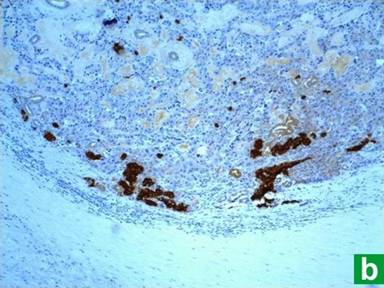

A 64-year-old woman was admitted to our hospital in 2000 for evaluation of severe epigastric pain, chronic diarrhea and a 11.5 kg weight loss over last few years. Past medical and family history were unrevealing for any endocrine tumors. Esophagogastroduodenoscopy showed severe duodenitis and an atypical post-bulbar ulcer. Because of the classic presentation, atypical peptic ulcer disease and chronic diarrhea with weight loss, we pursued a work-up for Zollinger-Ellison syndrome. Her serum gastrin level was elevated (198 pg/mL; reference range: 0-42 pg/mL). CT scan of the abdomen and endoscopic retrograde cholangiopancreatography showed a 3 cm mass in the head of the pancreas compressing the main pancreatic duct. Subsequent octreotide scan revealed an octreotide positive mass in head of the pancreas suggestive of a neuroendocrine tumor. Serum insulin, glucagon, somatostatin and vasointestinal polypeptide (VIP) levels were within normal range. She underwent a Whipple procedure in 2000 with resection of the mass that proved to be a 2.8 cm gastrinoma with focal venous and perineural invasion (Figure 1). All resected lymph nodes were negative on H&E and immunostaining (Figure 2). Immunohistochemically, tumor cells were diffusely positive for gastrin, and focally positive for chromogranin-A, synaptophysin and insulin (Figure 3). Tumor cells were negative for glucagon, VIP or somatostatin. Post-operatively, follow-up serum gastrin level was suppressed (18 pg/mL). She received no adjuvant chemotherapy or radiotherapy.

Figure 3. Immunohistochemistry demonstrates diffusely positive staining for gastrin (a.), and focally positive for insulin (b.). |